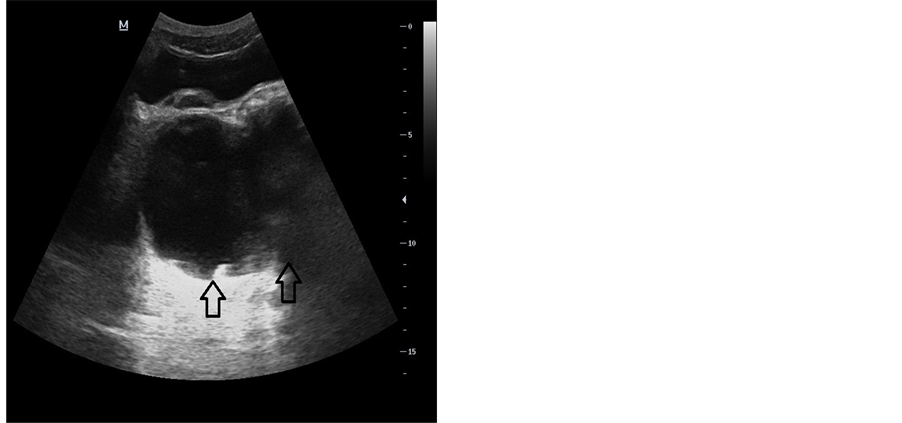

A 33-year-old man applied to our hospital with the complaints of a long-lasting constipation and a nonspecific lower abdominal pain. His physicals did not reveal any abnormalities, and his routine laboratory work-up was within normal limits. The patient was examined by ultrasonography (US) (DC-7, Mindray Ltd., China). US examination disclosed a cystic mass of a size of 6.0 × 7.5 × 7.5 cm, at the posterior aspect of the bladder. The lesion was extending to the presacral space posteriorly, and had a bilobulated appearance at this site (Figure 1). No solid components could be visualized in the cyst. Although an ASM was among the differential list, a Computed Tomography (CT) examination was planned because other differential diagnostic possibilities could not yet be ruled out at this level of the evaluation. CT examination was performed with a 16-row multidetector scanner (Somatom Sensation 16, Siemens AG, Germany). CT revealed a bony defect at the anterior part of the sacral bone, together with a presacral cystic mass which demonstrated a connection with the dural sac (Figure 2). Magnetic Resonance Imaging (MRI) examination was done in a 1.5 Tesla (T) MRI system (Magnetom, Siemens AG, Germany). At MRI, a cystic mass which was hypointense on T1-weighted (T1W), and hyperintense on T2-weighted (T2W) sequences at the presacral space was demonstrated. Sagittal images clearly demonstrated that the cyst was in connection with the dural sac through the bony defect at the sacrum (Figure 3). It was also noted that the spinal cord was low-lying and ending at the level of the lower plate of the L5 vertebral body (Fig- ure 4). After intravenous contrast injection, no solid or neural components could be visualized in the mass. The axial T1W images showed that the mass was exerting pressure on the rectum (Figure 5). An anteroposterior (AP) pelvis radiogram demonstrated a sacral deformity and the scimitar sign (Figure 6). Upon these imaging findings, the patient got the diagnosis of an anterior sacral meningocele. The neurologic examination of the patient revealed no deficits. The patient was provided satisfying information concerning the necessity of surgery and follow-up. But, rejecting the idea of surgery, the patient, who demonstrated no clinical symptoms other than constipation, was put into a follow-up program. The patient was followed by US for a year, and no progression in the lesion size was detected during this time period.

Figure 1. A bilobulated anechoic cystic mass is present at the posterior aspect of the bladder (arrows).

The pelvic cystic mass is easily demonstrated at US. But in order to make a definitive diagnosis, the relation of the mass with the dural sac must be disclosed well. Especially those cysts with narrow necks may be mistaken for an ovarian cyst or a full bladder [2] [4] [14] . It is very important to make a definitive differential diagnosis of an ASM in pelvic cystic masses. This is because in patients who suffer from this disease and who lack this differential evaluation, a surgical or an interventional approach may lead to very serious complications such as a meningitis or a sudden fall in intracranial pressure [6] [9] [15] . US is also very valuable in the follow-up of patients who are not scheduled for surgery [4] . CT may demonstrate the bony abnormalities at the anterior sacral wall in a much better fashion than any other imaging modality. Administration of intrathecal contrast media may disclose the relation of the dural sac and the presacral cyst perfectly. It may also help detect any solid components of the cystic mass [4] . But since CT myelography is an invasive procedure and utilizes ionizing radiation, it must be saved for those cases with cysts with a narrow neck which present difficulties in the detection of the relation of the cyst and the thecal sac [12] .